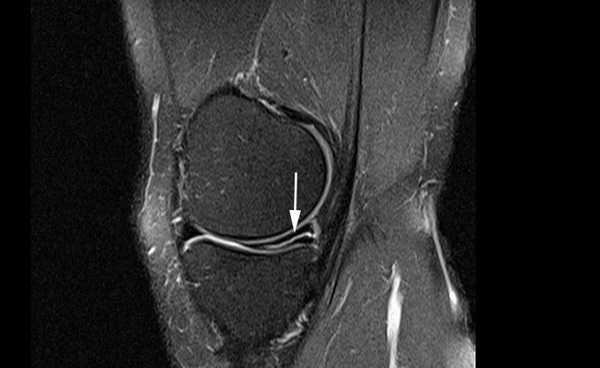

Разрыв заднего рога медиального мениска на снимке МРТ

Лечение зависит от степени поражения. При I и II специалисты рекомендуют консервативные методы и покой, III стадия требует хирургического вмешательства.

При подозрении на разрыв мениска назначают МРТ коленного сустава. Томограммы визуализируют малейшие нарушения целостности хрящевой пластины.

В результате магнитно-резонансной томографии получают послойные изображения коленного сустава, выполненные в трех взаимно перпендикулярных проекциях. Снимки отражают состояние связочного аппарата, капсулы, менисков, кровеносных сосудов и нервных волокон. Благодаря резонансу заряженных частиц в молекулах воды МРТ показывает уровень синовиальной жидкости, позволяет диагностировать осложнения травмы хрящевой пластины (гемартроз, образование кисты и пр.).

Признаком повреждения мениска служит наличие линейного гиперинтенсивного очага на Т2-взвешенных изображениях. Участок сообщается с суставной поверхностью хряща, линию разрыва прослеживают на двух и более сканируемых срезах. При этом наблюдают деформацию и фрагментацию пластины.

Разрыв заднего рога медиального хряща на снимках, выполненных в разных режимах, стрелка указывает на нарушение целостности пластины